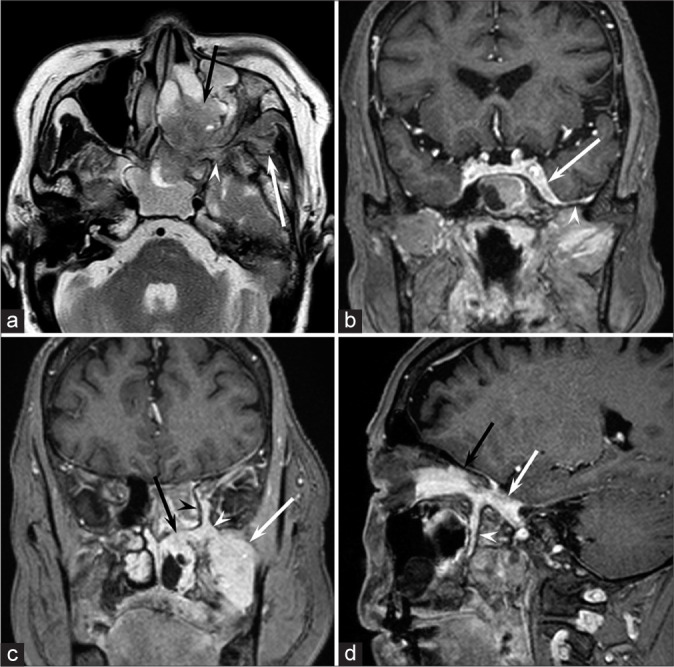

We report a case of a 73-year-old woman presenting with intracranial and extracranial meningioma with perineural spread crossing the foramen rotundum and pterygopalatine fossa, primarily along the maxillary nerve. She visited our hospital with the chief complaint of the left cheek swelling. Subsequent magnetic resonance imaging revealed a well-demarcated mass containing intracranial (cavernous sinus, Meckel's cave, and middle cranial fossa) and extracranial components (pterygopalatine fossa, orbit, nasal cavity, ethmoid and sphenoid sinuses, infratemporal fossa, and buccal space) through the foramen rotundum. A biopsy specimen was obtained from the cheek mass, and the histopathological diagnosis was meningothelial meningioma.